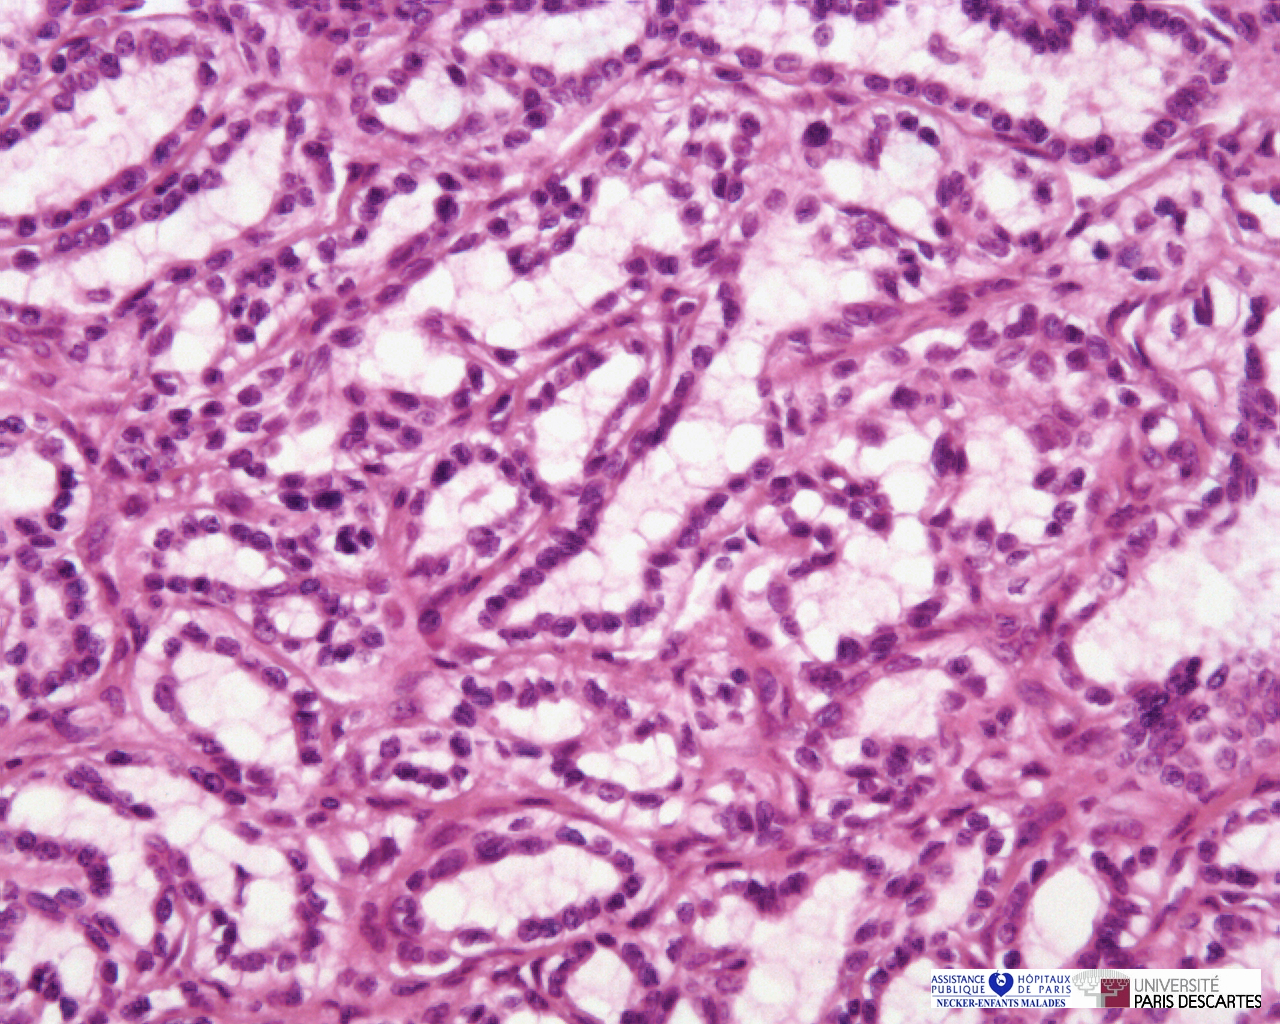

Edged by the consensus committees and a new definition of renal adenoma was proposed. tered malignant renal neoplasm comprising up to 70% of large series [3]. current definitive classification of renal cell neoplasia. 9 Delahunt B, Eble JN. Papillary adenoma of the kidney. J. ... Read Here